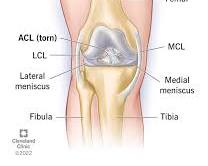

ACL(Anterior Cruciate Ligament)とは、膝関節の前十字靭帯のことで、膝の安定性を保つ上で非常に重要な靭帯です。スポーツ活動中などに強い力が加わると断裂してしまうことがあります。スポーツ中の急な方向転換やジャンプ、膝に直接強い衝撃を受けた場合の受傷が特に多いです。

新しいウィンドウで開くmy.clevelandclinic.org